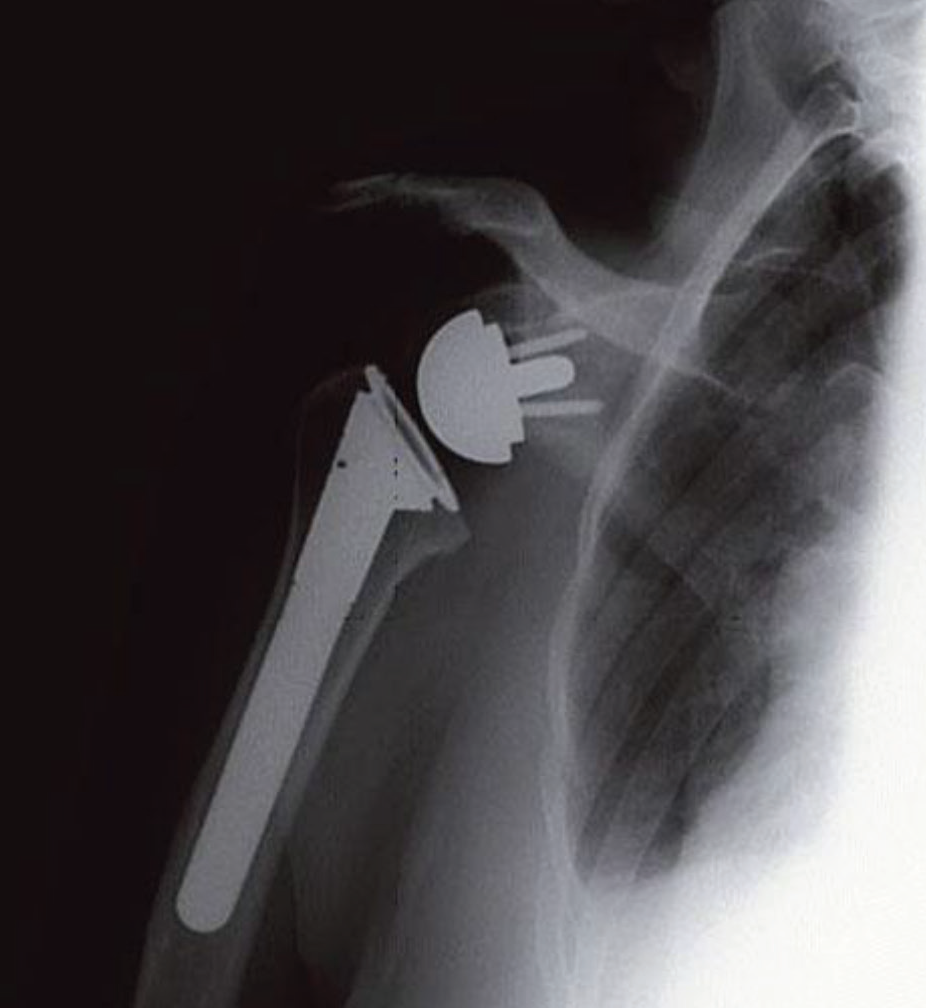

Ters Omuz Protezi: Standart bir total omuz protezinin omuz eklemi etrafındaki kasların ve tendonların sağlam olması durumunda uygulanmasına karşılık, ters omuz protezi rotator manşetin yırtıldığı veya arızalandığı durumlar için tasarlanmıştır. Standart bir total omuz protezi ameliyatında metal baş kol kemiğinin üst kısmına, plastik soket ise kürek kemiğine bağlanır. Ters omuz protezinde ise, baş eklemin yuva tarafına yerleştirilir. Bu, doğada bulunduğu yerin tam tersidir. Soket daha sonra kol kemiğindeki (humerus) metal bir sap tarafından desteklenecek şekilde kol tarafına yerleştirilir.

Ters omuz protezi. Rotator manşetin tam olarak yırtıldığı ve işlevini yerine getiremediği durumlarda yapılır.